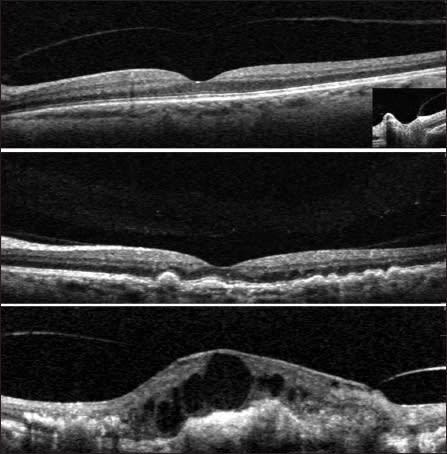

Currently, approximately 500,000 patients in the United States and Europe have symptomatic VMA,13 many of whom may benefit from the novel nonsurgical procedure of a single office-based intravitreal injection of ocriplasmin. These patients can reasonably expect to obtain improvement or resolution of symptoms before they have to decide whether to undergo the standard treatment of surgical vitrectomy (Figure 2).

Figure 2. OCT images of a case with VMT that was successfully treated with oicrplasmin The patient was 20/80 pre-Rx (upper left), 20/80 one week later (upper right; VMT resolved within 24 hours), 20/40 one month later (lower left), and 20/30 three months (lower right), The patient was 20/20 12 months after treatment. Images courtesy of Carl D. Regillo, MD.